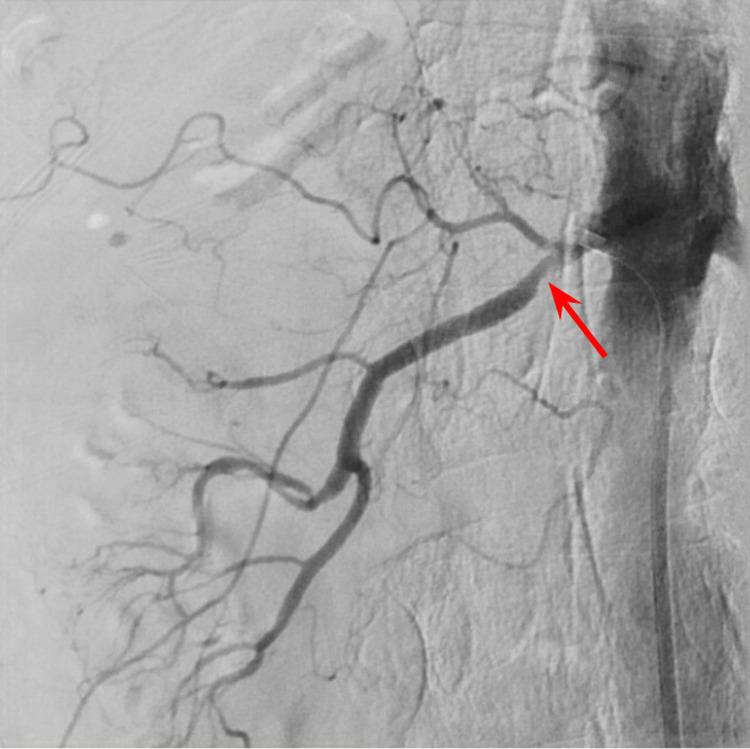

Renal artery stenosis (RAS) is one of the major causes of resistant/malignant hypertension. It can be described as atherosclerotic or non-atherosclerotic. Atherosclerotic RAS comprises almost 90% of all RAS cases and is a prevalent disease of the elderly. Multiple risk factors contribute to atherosclerosis development, which leads to the release of renin and aldosterone, causing resistant/malignant hypertension. Early recognition is prudent but challenging as there are no early clinical signs. We believe that renal resistive index with supportive clinical, laboratory, and imaging modalities can help select revascularization patients.

肾动脉狭窄(RAS)是顽固性/恶性高血压的主要病因之一。它可分为动脉粥样硬化性或非动脉粥样硬化性。动脉粥样硬化性RAS约占所有RAS病例的90%,是一种常见的老年疾病。多种危险因素促成动脉粥样硬化的发展,进而导致肾素和醛固酮的释放,引起顽固性/恶性高血压。由于没有早期临床症状,早期识别虽谨慎但具有挑战性。我们认为,结合支持性的临床、实验室和影像学检查手段的肾阻力指数有助于选择进行血运重建的患者。